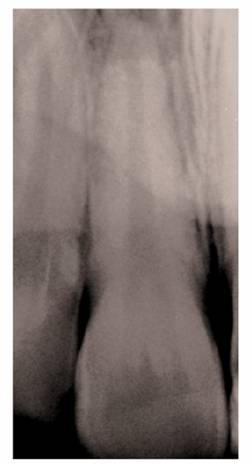

Precementation Radiographs

Prior to cementation, Yamada (personal communication, 2001) re-radiographs the

prepared teeth (Figures 19-25A

and B).

These images check the pulpal, periapical, and periodontal status of the teeth.

Also, the radiographs, unencumbered by the presence of the metal castings,

provide a chamber/canal road map record if the tooth requires endodontics in

the future. This may appear pessimistic, but Arens and Chivian reported that

over 40% of teeth requiring root canal therapy are crowned.4 Prior

knowledge of the size, location, and direction of the chamber and the canal will

reduce the possibility of (1) crown damage during access opening, (2) lost time

searching for the canal orifice, (3) perforations of the chamber or the canal

because of disorientation, (4) natural core elimination by gutting, (5) crown

dislodgment, and (6) sufficient destruction to alter the situation and require

corrective surgery. Each of these iatrogenic possibilities reduces the

prognosis and jeopardizes the tooth's reliability as an abutment.

Figure 19-25A and B: Precementation radiographs provide a road map to the canals if endodontic therapy is necessary after cementation of the castings. (Radiographs courtesy of Dr. Henry Yamada.)